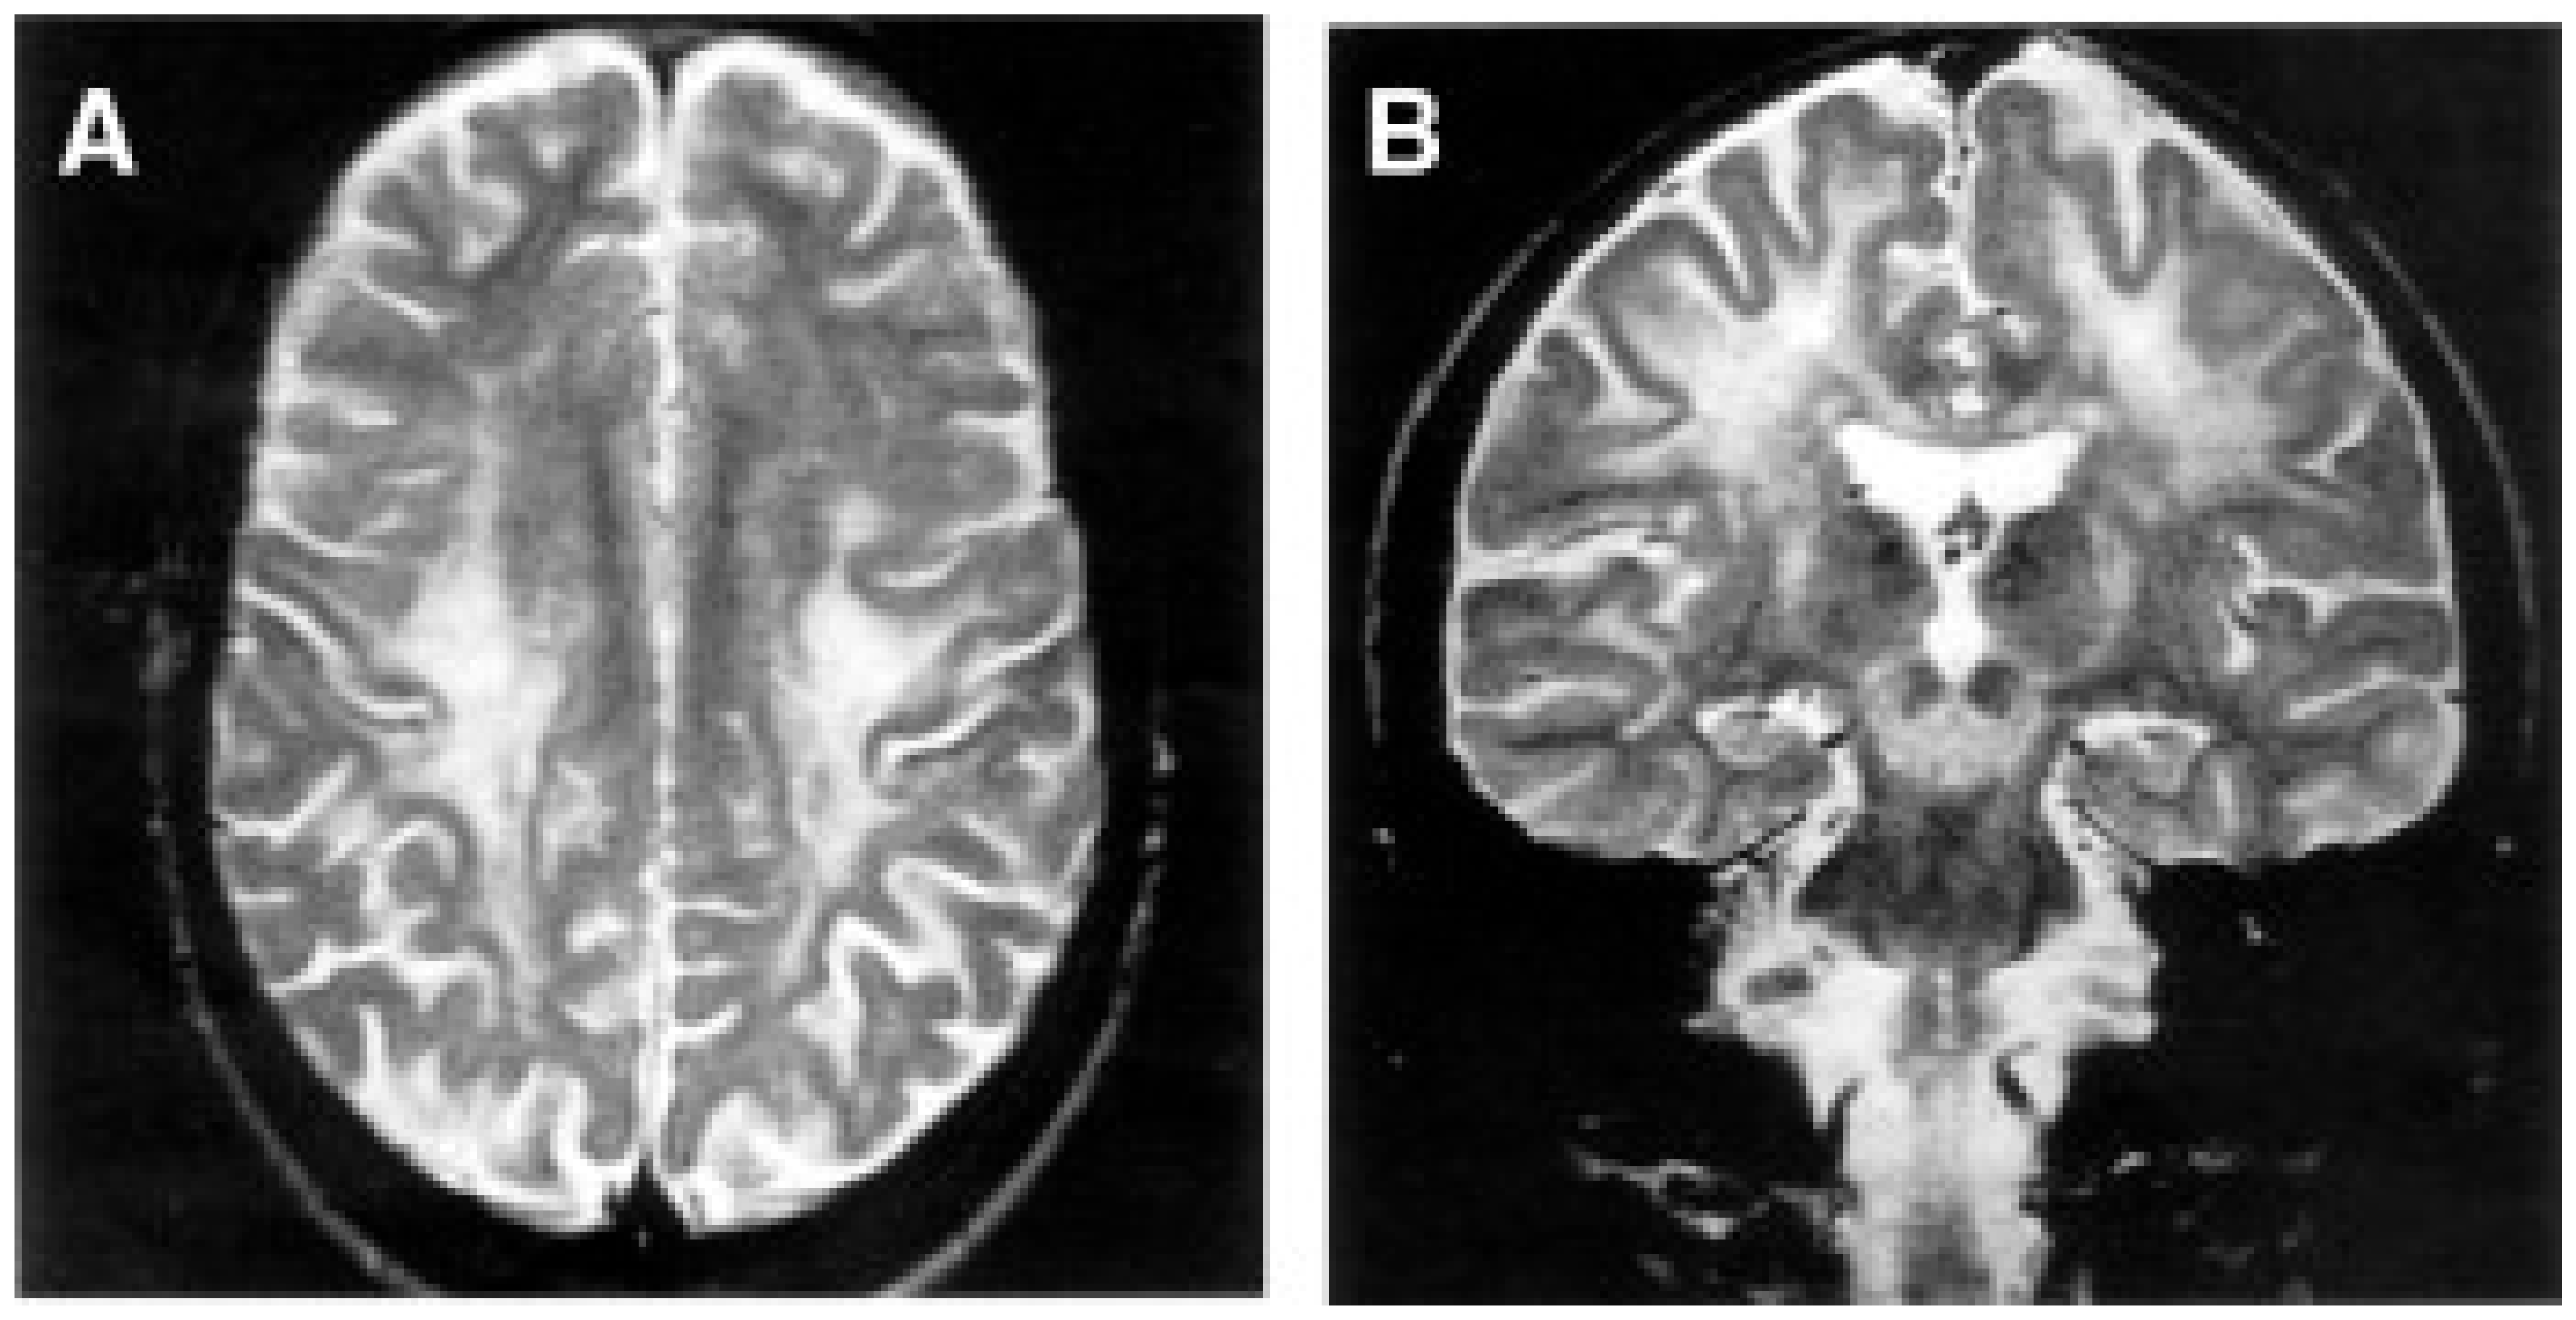

- Uziel, G.; Moroni, I.; Lamantea, E.; Fratta, G.M.; Ciceri, E.; Carrara, F.; Zeviani, M. Mitochondrial Disease Associated with the T8993G Mutation of the Mitochondrial ATPase 6 Gene: A Clinical, Biochemical, and Molecular Study in Six Families. J. Neurol. Neurosurg. Psychiatry 1997, 63, 16–22. [Google Scholar] [CrossRef] [PubMed]

- Holt, I.J.; Harding, A.E.; Petty, R.K.; Morgan-Hughes, J.A. A New Mitochondrial Disease Associated with Mitochondrial DNA Heteroplasmy. Am. J. Hum. Genet. 1990, 46, 428–433. [Google Scholar] [PubMed]

- de Vries, D.D.; van Engelen, B.G.; Gabreëls, F.J.; Ruitenbeek, W.; van Oost, B.A. A Second Missense Mutation in the Mitochondrial ATPase 6 Gene in Leigh’s Syndrome. Ann. Neurol. 1993, 34, 410–412. [Google Scholar] [CrossRef] [PubMed]

- Tatuch, Y.; Christodoulou, J.; Feigenbaum, A.; Clarke, J.T.; Wherret, J.; Smith, C.; Rudd, N.; Petrova-Benedict, R.; Robinson, B.H. Heteroplasmic MtDNA Mutation (T----G) at 8993 Can Cause Leigh Disease When the Percentage of Abnormal MtDNA Is High. Am. J. Hum. Genet. 1992, 50, 852–858. [Google Scholar] [PubMed]